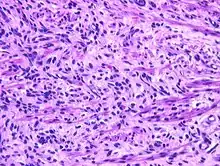

Fetal rhabdomyoma are separated into two histologic types: Myxoid and cellular.[7][8] However, irrespective of histologic type, these tumors almost never show necrosis or increased mitoses. However, a cambium layer, abnormal mitoses and nuclear pleomorphism is not seen.

Cellular fetal rhabdomyomas are composed of bland, primitive spindled cells. The spindle cells are haphazardly arranged primitive, elongated skeletal muscle cells. The cells are set within a well-developed fibromyxoid stroma. A different pattern (intermediate type) is predominantly composed of cells with better differentiation towards skeletal muscle. There are often large ganglion cell-like rhabdomyoblasts showing prominent nucleoli within nuclei that show vesicular chromatin distribution. Another population includes strap-like rhabdomyoblasts with darkly staining pink cytoplasm. Nearly all tumors show short to more sweeping fascicles of spindled rhabdomyoblasts. The tumor cells may infiltrate into adjacent skeletal muscle or fat. It is not uncommon to see peri-neural association, although not perineural infiltration.[9]